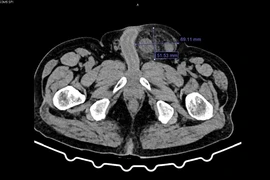

Chủ quan với khối thoát vị bẹn người đàn ông bị hoại tử đại tràng

Thoát vị bẹn gặp ở mọi lứa tuổi cần đề phòng biến chứng nghẹt hoại tử ruột, hoại tử tinh hoàn, gây tắc ruột, đau dữ dội và có nguy cơ đe dọa tính mạng.